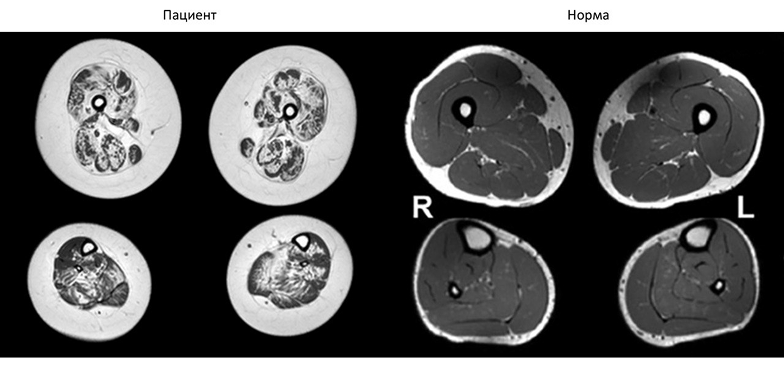

МРТ мышц: на аксиальных срезах в режиме Т1 выраженная диффузная атрофия мышц бедер (посмотреть рисунок)

МРТ мышц